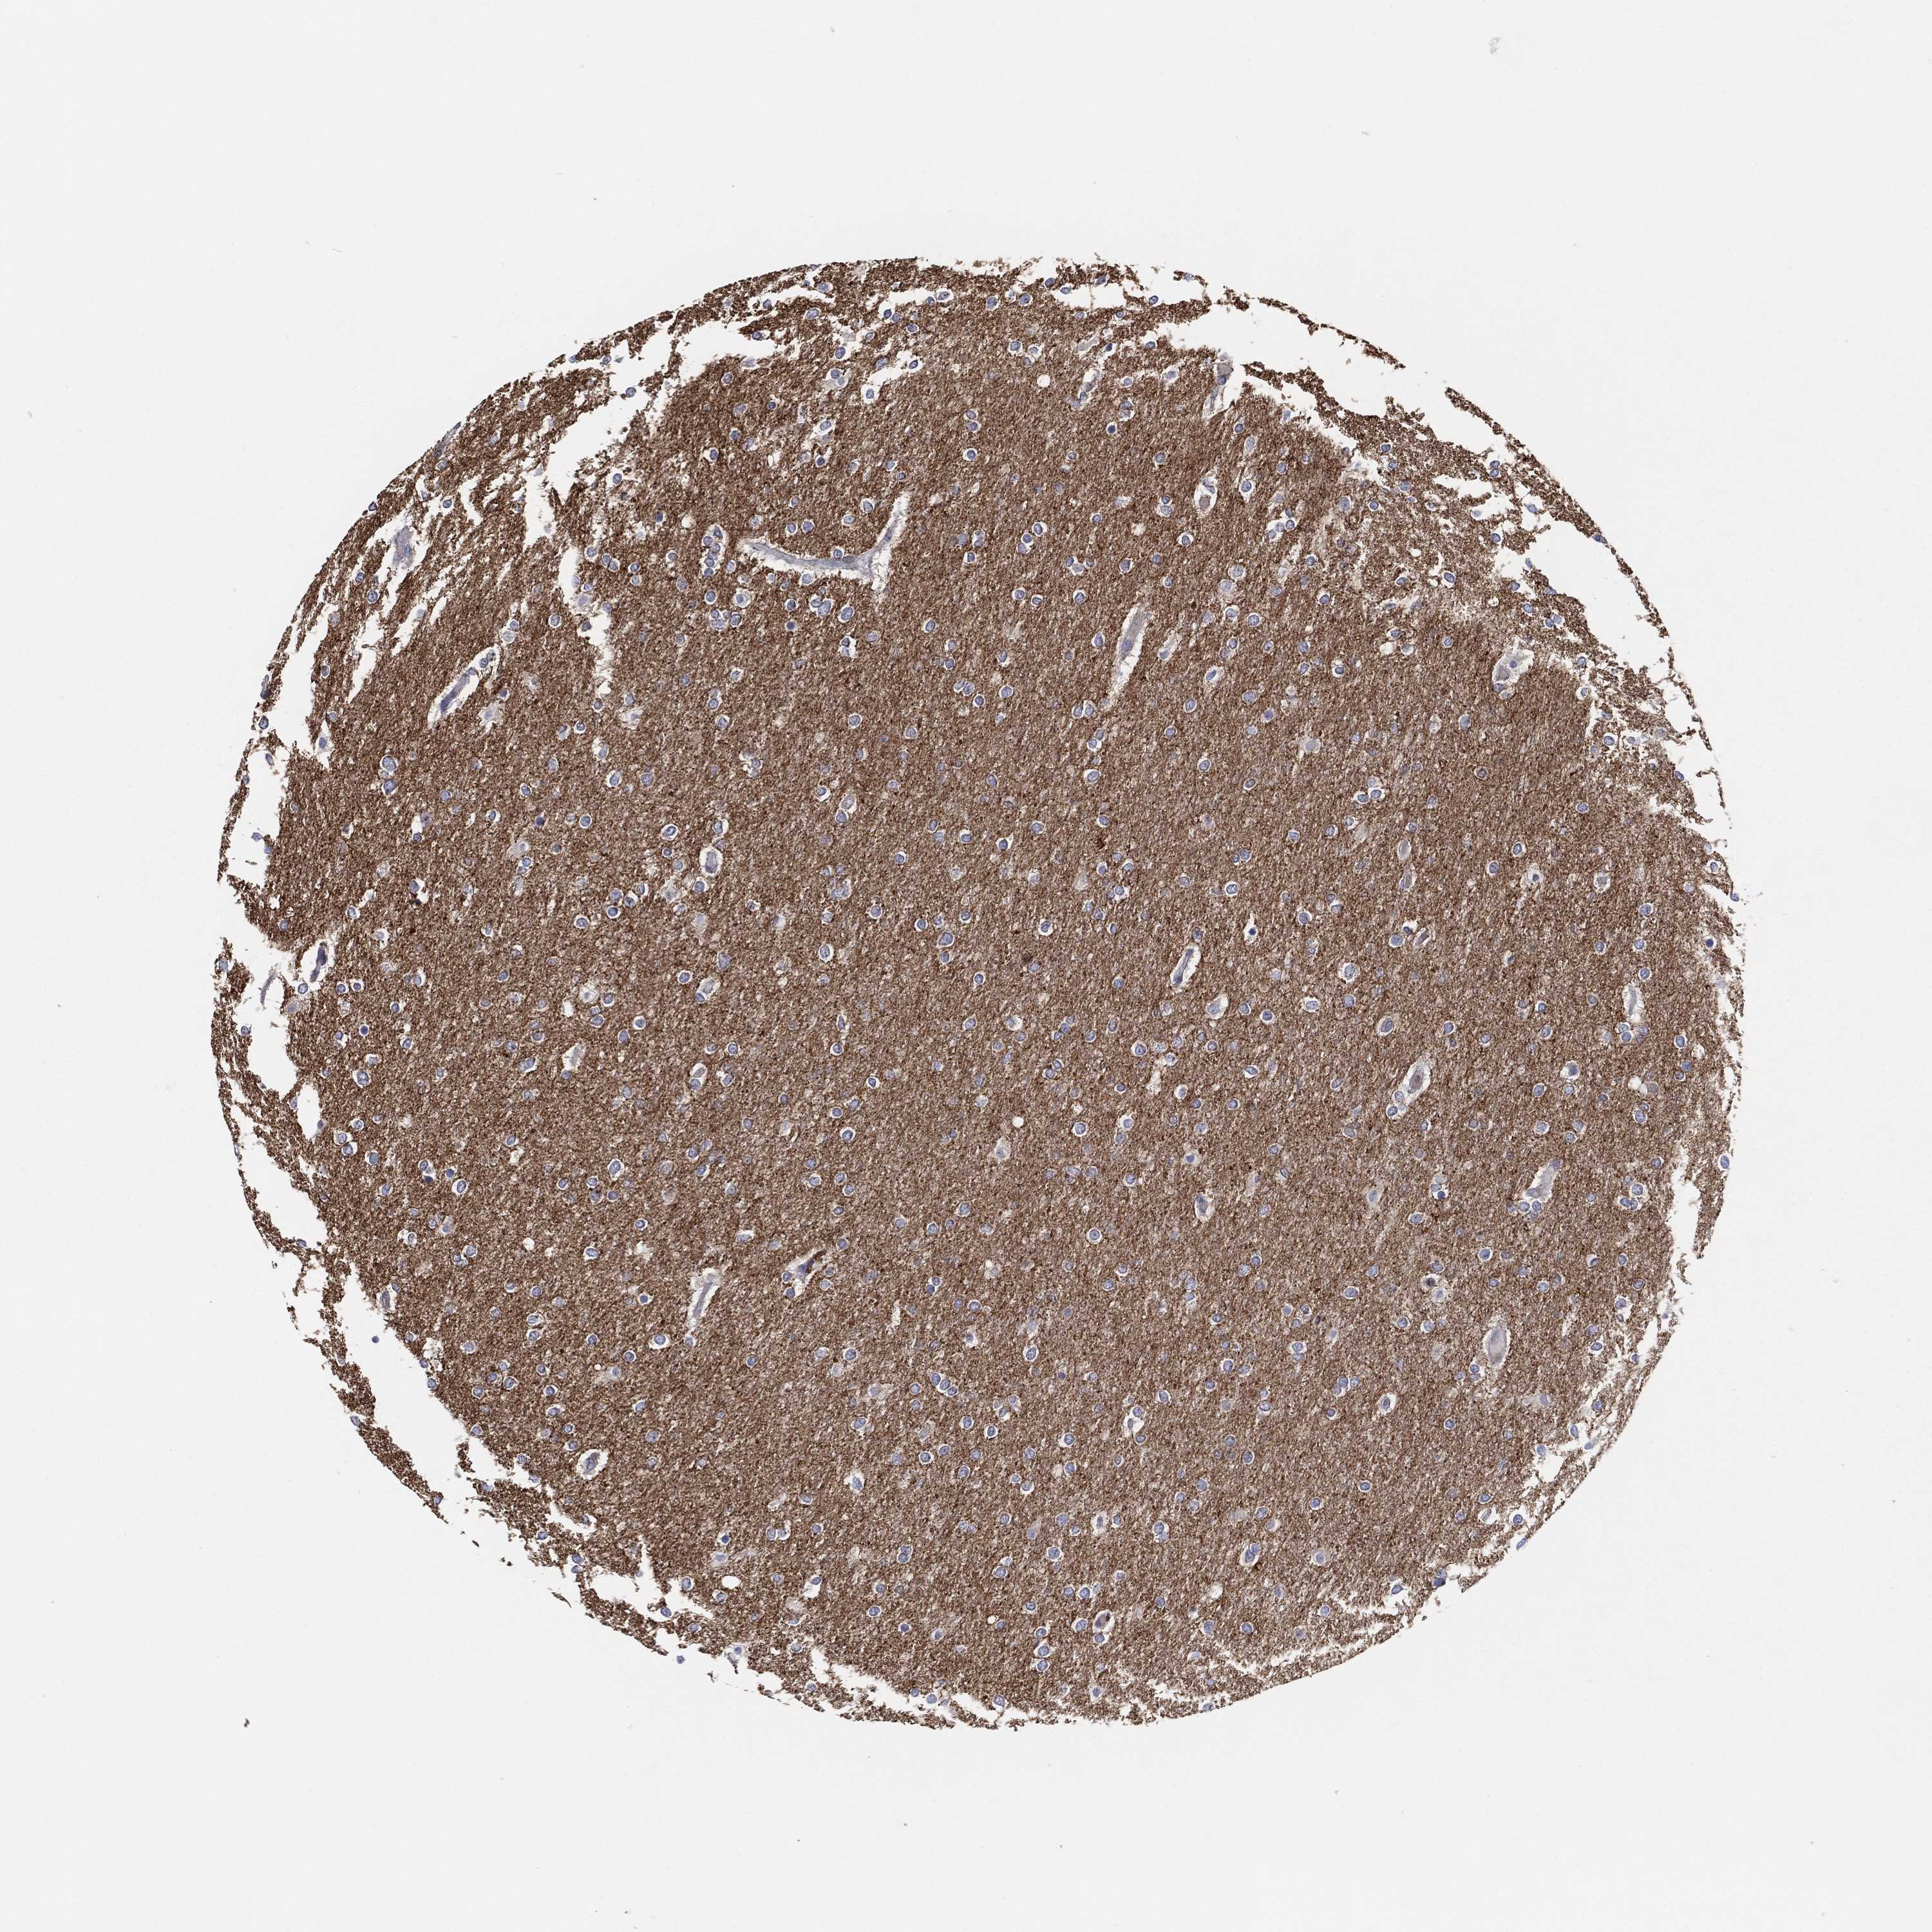

GLIOMA - Protein expressioni

A mouse-over function shows sample information and annotation data. Click on an image to view it in a full screen mode. Samples can be filtered based on level of antibody staining by selecting one or several of the following categories: high, medium, low and not detected. The assay and annotation is described here.

Note that samples used for immunohistochemistry by the Human Protein Atlas do not correspond to samples in the TCGA dataset.

Antibody stainingi

Antibody staining in the annotated cell types in the current human tissue is reported as not detected, low, medium, or high, based on conventional immunohistochemistry profiling in selected tissues. This score is based on the combination of the staining intensity and fraction of stained cells.

Each image is clickable and will lead to virtual microscopy that enables deeper exploration of all samples and also displays staining intensity scores, fraction scores and subcellular localization as well as patient and tissue information for each sample.

Antibody HPA063924

Staining

High

Medium

Low

Not detected

Intensity

Strong

Moderate

Weak

Negative

Quantity

>75%

75%-25%

<25%

None

Location

Nuclear

Cytoplasmic/membranous

Cytoplasmic/membranous,nuclear

Glioma, malignant, Low grade

Glioma, malignant, High grade